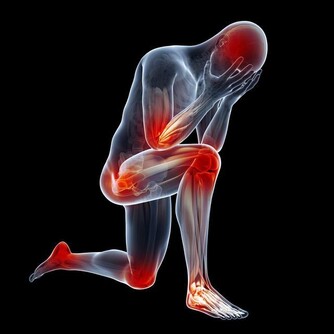

中指偏曲、指間漏縫:循環系統功能較差,還會影響腸道功能。

無名指偏曲、指間漏縫:泌尿系統功能較弱,也容易出現神經衰弱、頭痛、失眠等症狀。

小指短小:提示生育機能弱,腎氣不足,易患頭暈、耳鳴、腰腿酸痛等病。